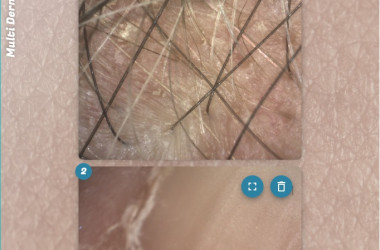

- Kamera za kožo Visioscope® PC 35

Opremljeno z vzporedno in navzkrižno polarizirano svetlobo:

- Vzporedno polarizirana svetloba vizualizira površinsko strukturo kože

- Navzkrižno polarizirana svetloba razkriva globlje plasti kože, kot so pigmentacija in vaskularne strukture

Načine osvetlitve lahko takoj spremenite s pritiskom na gumb kamere. Na podlagi zajetih slik programska oprema izvede enostavno in objektivno analizo slik gub, por in pigmentnih madežev. Popeljite svoje stranke na vizualno potovanje po obrazu in telesu.

Kamera je popolna tudi za pregledovanje stanja las in lasišča, kot so poškodbe las, prhljaj ali razdraženo lasišče.

- Kvantitativna analiza s posebnimi trakovi

Trakovi Sebufix® in Corneofix®, dobavljeni v praktičnih podajalnikih, se uporabljajo v kombinaciji s kamero Visioscope® za zagotavljanje jasnih vizualnih rezultatov nastajanja sebuma in luščenja kože, ki jih je strankam enostavno razložiti.

Sebufix® F 16 prikazuje nastajanje sebuma v realnem času

Corneofix® F 20 omogoča podrobno analizo deskvamacije in suhosti.